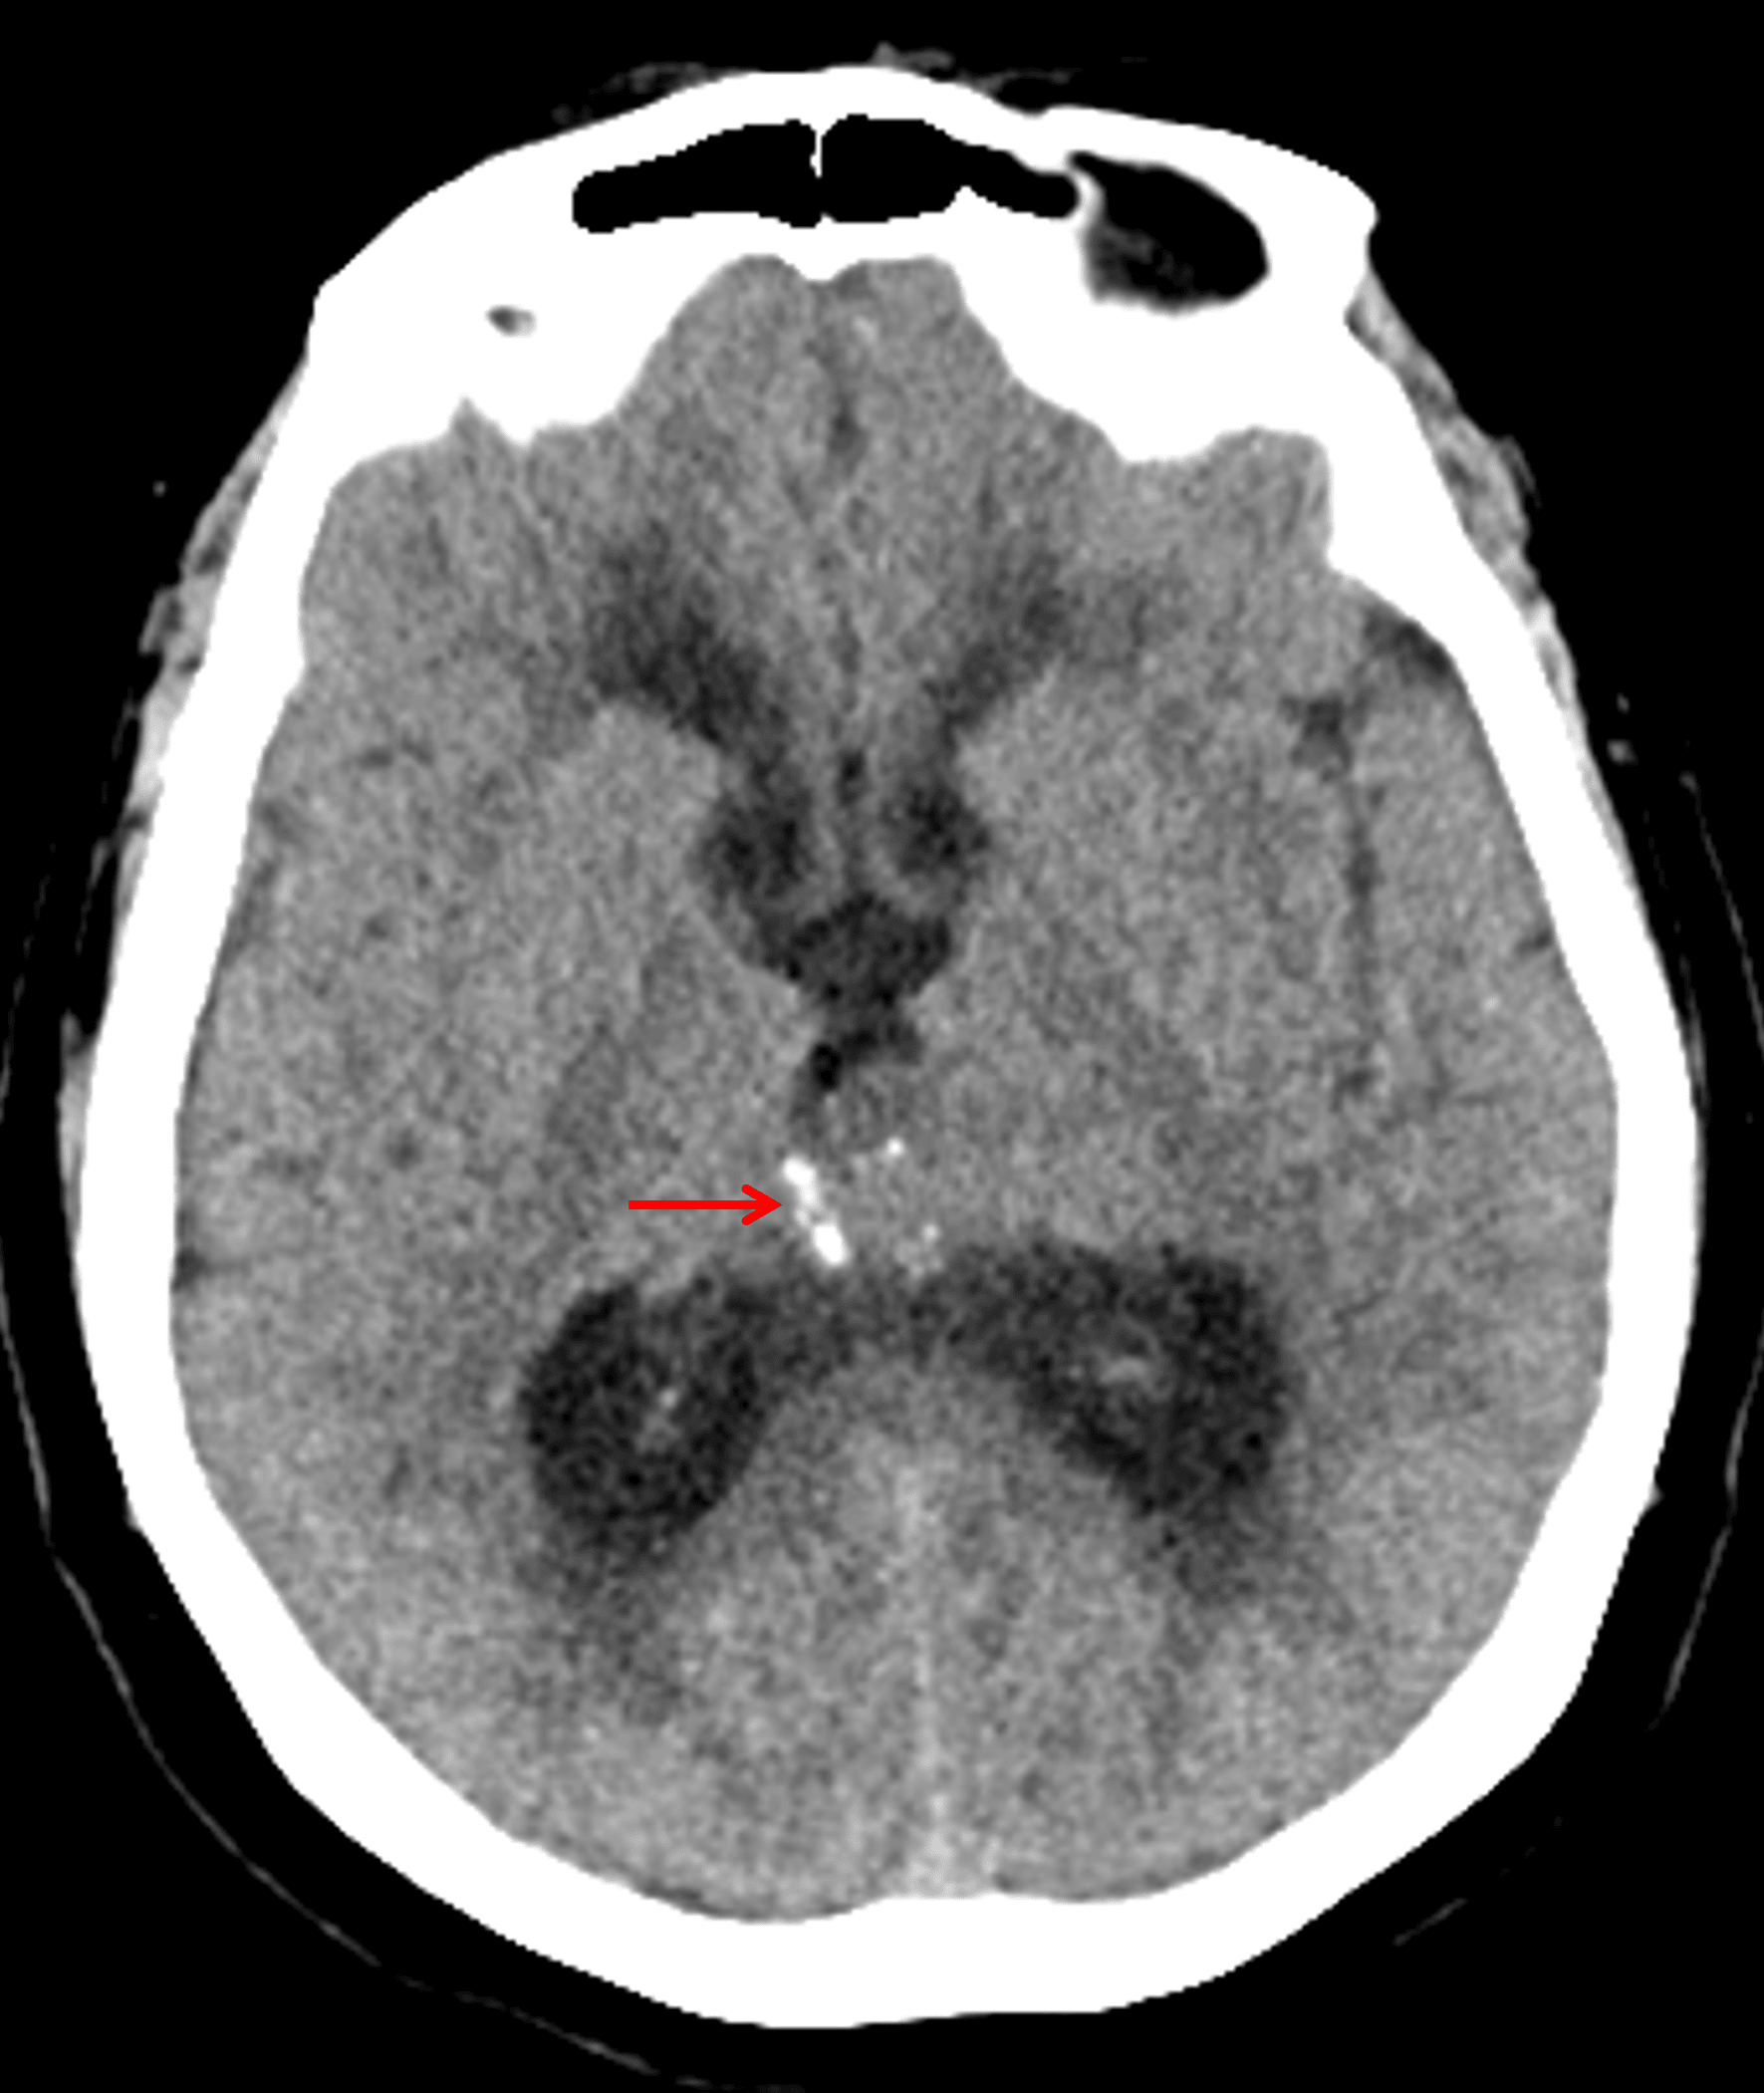

CT

- Pineal region mass with peripheral calcification

- Associated obstructive hydrocephalus

A pineal region mass with peripheral calcification (red arrow) is identified on CT.